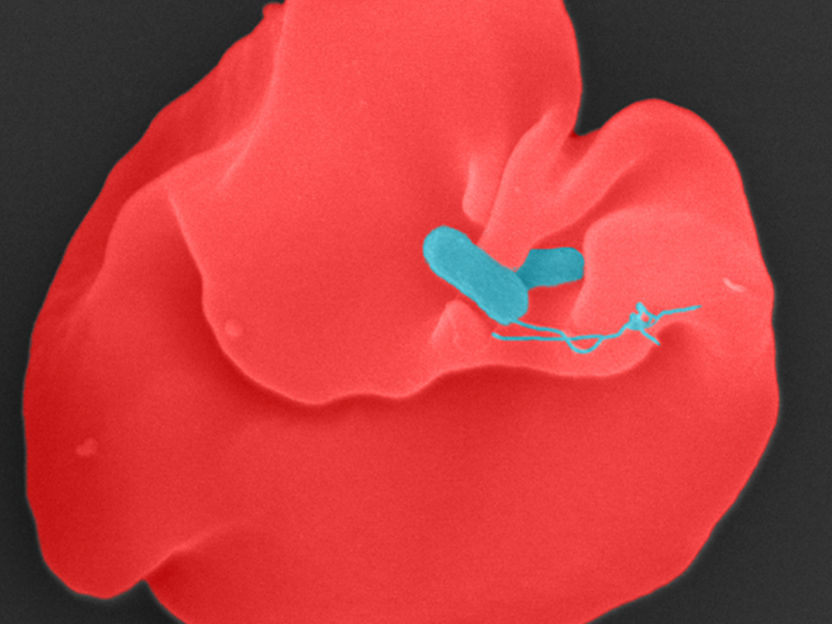

Bartonella bacilliformis (blau) infiziert einen menschlichen Erythrozyten.

Juergen Berger, Max Planck Institute for Biology, Tübingen, Germany, CC-BY 4.0